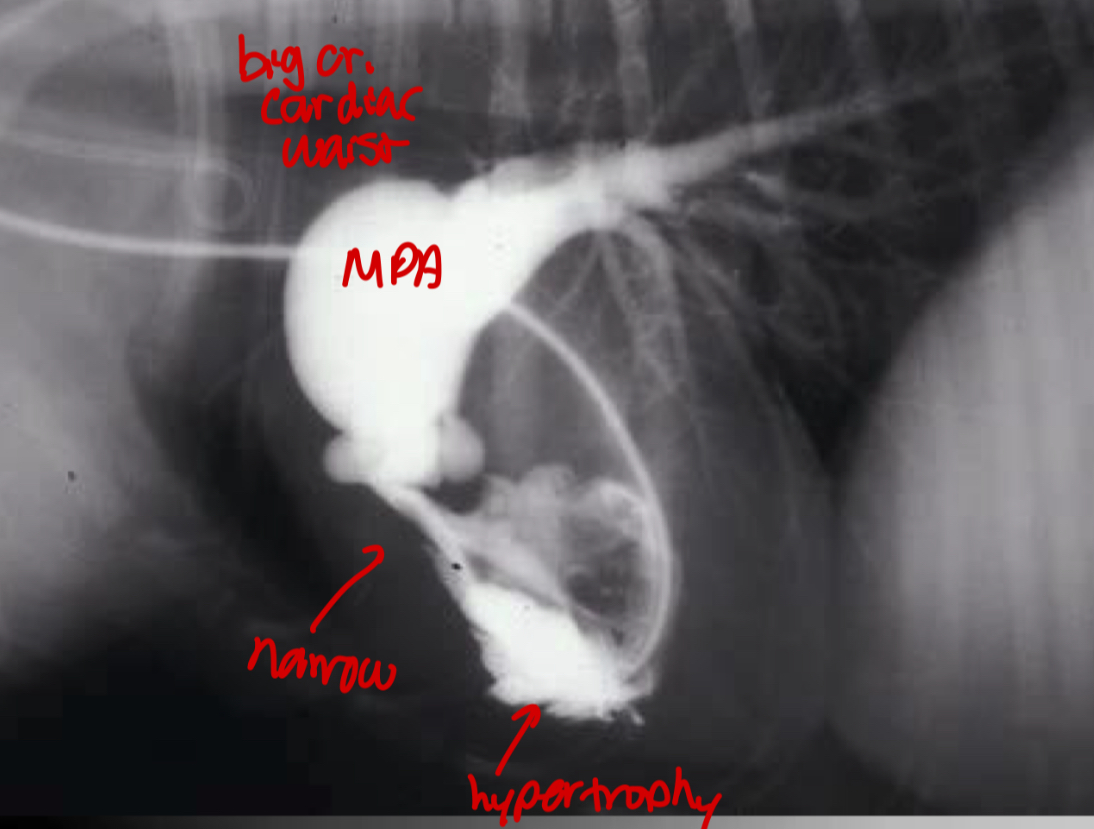

What fails to happen at birth in PDA dogs

Failure of ductus arteriosus to close after birth —> persistent shunt between aorta and MPA

Which direction is the PDA shunt

Left to right (can flip later in disease but don’t worry about that)

Roentgen signs of PDA

-BIG LVE, VOLUME OVERLOAD

-triple bump sign on VD (Prox desc. Aorta, MPA, L.Au)

-normal to large pulmonary vessels (hyperperfusion)

±LHF

Pathogenesis of PDA

1.shunt connection between aorta and pul artery

2.high pressure blood from aorta to pul artery —> dilate pul artery

3.hyperperfused lungs

4.dumps blood into left heart

5.big LA and LV

What does the angiocardiography highlight in PDA

-see the shunt

-left ventricular dilation

-opacification of aortic and pulmonary arteries

What disease does this dog have

PDA